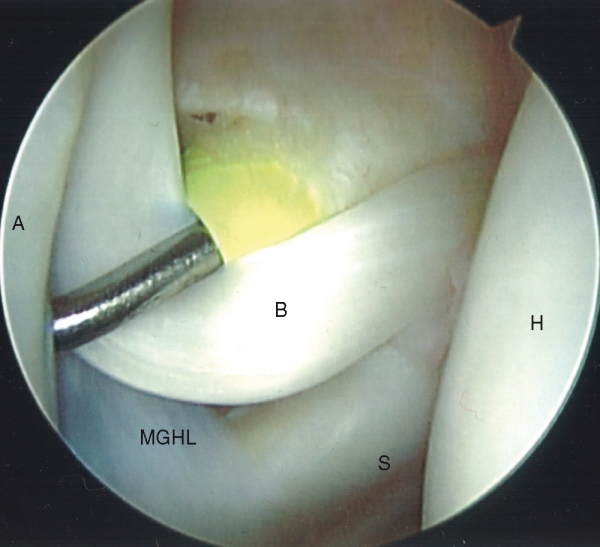

The middle glenohumeral ligament can also be variable in structure. At times, it may seem virtually nonexistent during arthroscopy. Commonly, it ranges from a sheet-like ligament to a robust cord-like structure as seen in a Buford complex (

Fig. 1-19

). With a Buford complex, the cord-like middle glenohumeral ligament originates high on the glenoid, and the anterior superior labrum is absent. It is important to recognize this as a normal anatomic variant. Erroneous diagnosis of this normal cord-like ligament as a labral tear and repair to the anterosuperior glenoid will result in significant restriction of normal motion.[15]